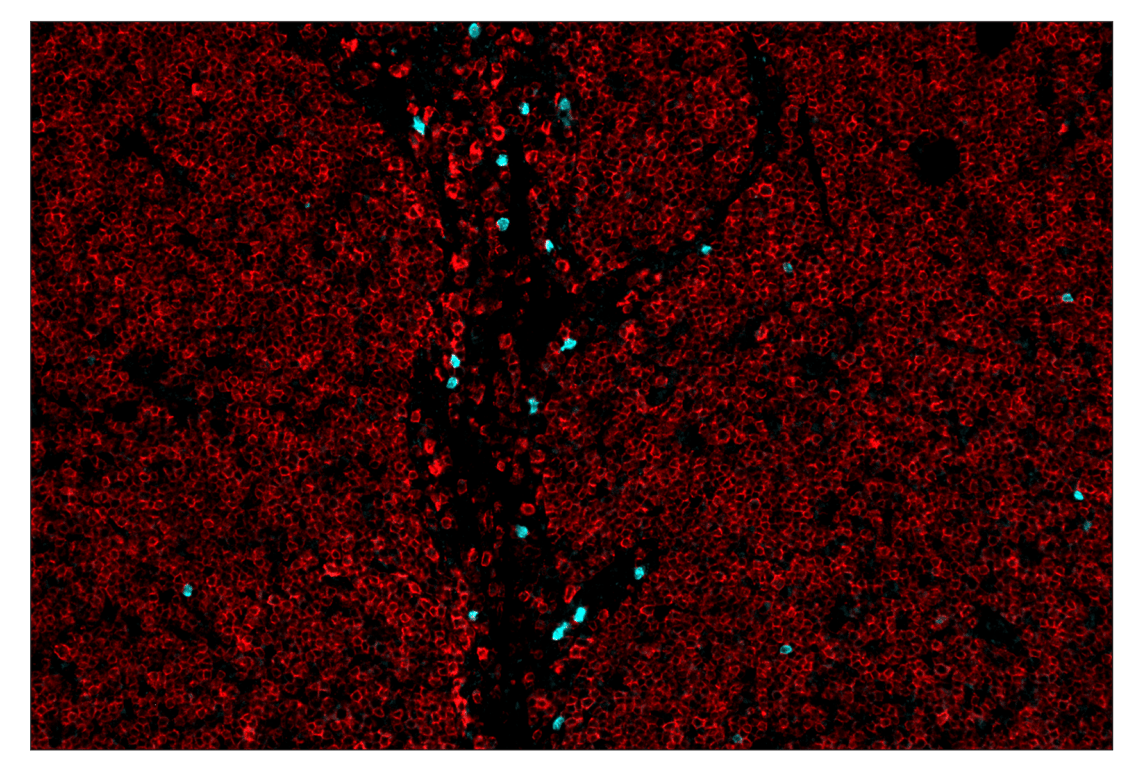

SignalStar™ multiplex immunohistochemical analysis of paraffin-embedded human lymph node using CD19 (Intracellular Domain) (D4V4B) & CO-0054-647 SignalStar™ Oligo-Antibody Pair #96289 (red) and Arginase-1 (D4E3M) & CO-0075-750 SignalStar™ Oligo-Antibody Pair #97934 (cyan). All fluorophores have been assigned a pseudocolor, as indicated.

Immunohistochemistry Image 2: Arginase-1 (D4E3M) & CO-0075-750 SignalStar<sup>™</sup> Oligo-Antibody Pair